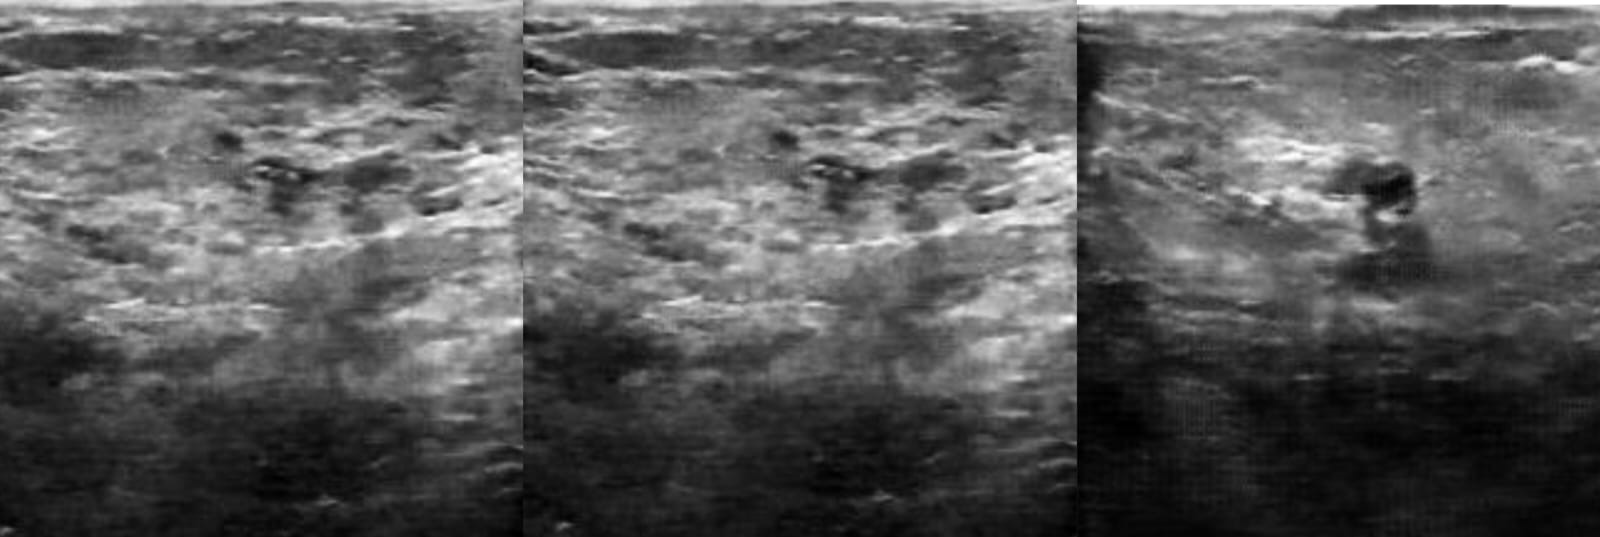

Lebih lanjut, dosen yang pernah mendapat penghargaan Satyalancana Karya Satya XX dari Presiden Republik Indonesia tersebut juga mengembangkan metode pembangkitan citra sintesis ultrasound dengan menggunakan metode yang sama. Penambahan variasi data latih pada metode ini bermanfaat untuk meningkatkan kinerja model prediksi.

Dalam hal ini, istri dari Elmison Sulaiman tersebut melakukan penelitian tentang model klasifikasi tingkat keparahan penyakit kanker payudara dari sebuah citra medis. Untuk menghasilkan model prediksi yang lebih akurat, diperlukan penambahan jumlah data latih pada setiap kategori citra ultrasound payudara hingga mendekati hasil yang seimbang.

Perkembangan model pendeteksi tingkat keparahan penyakit kanker payudara menggunakan citra sintesisis ultrasound dengan metode GAN